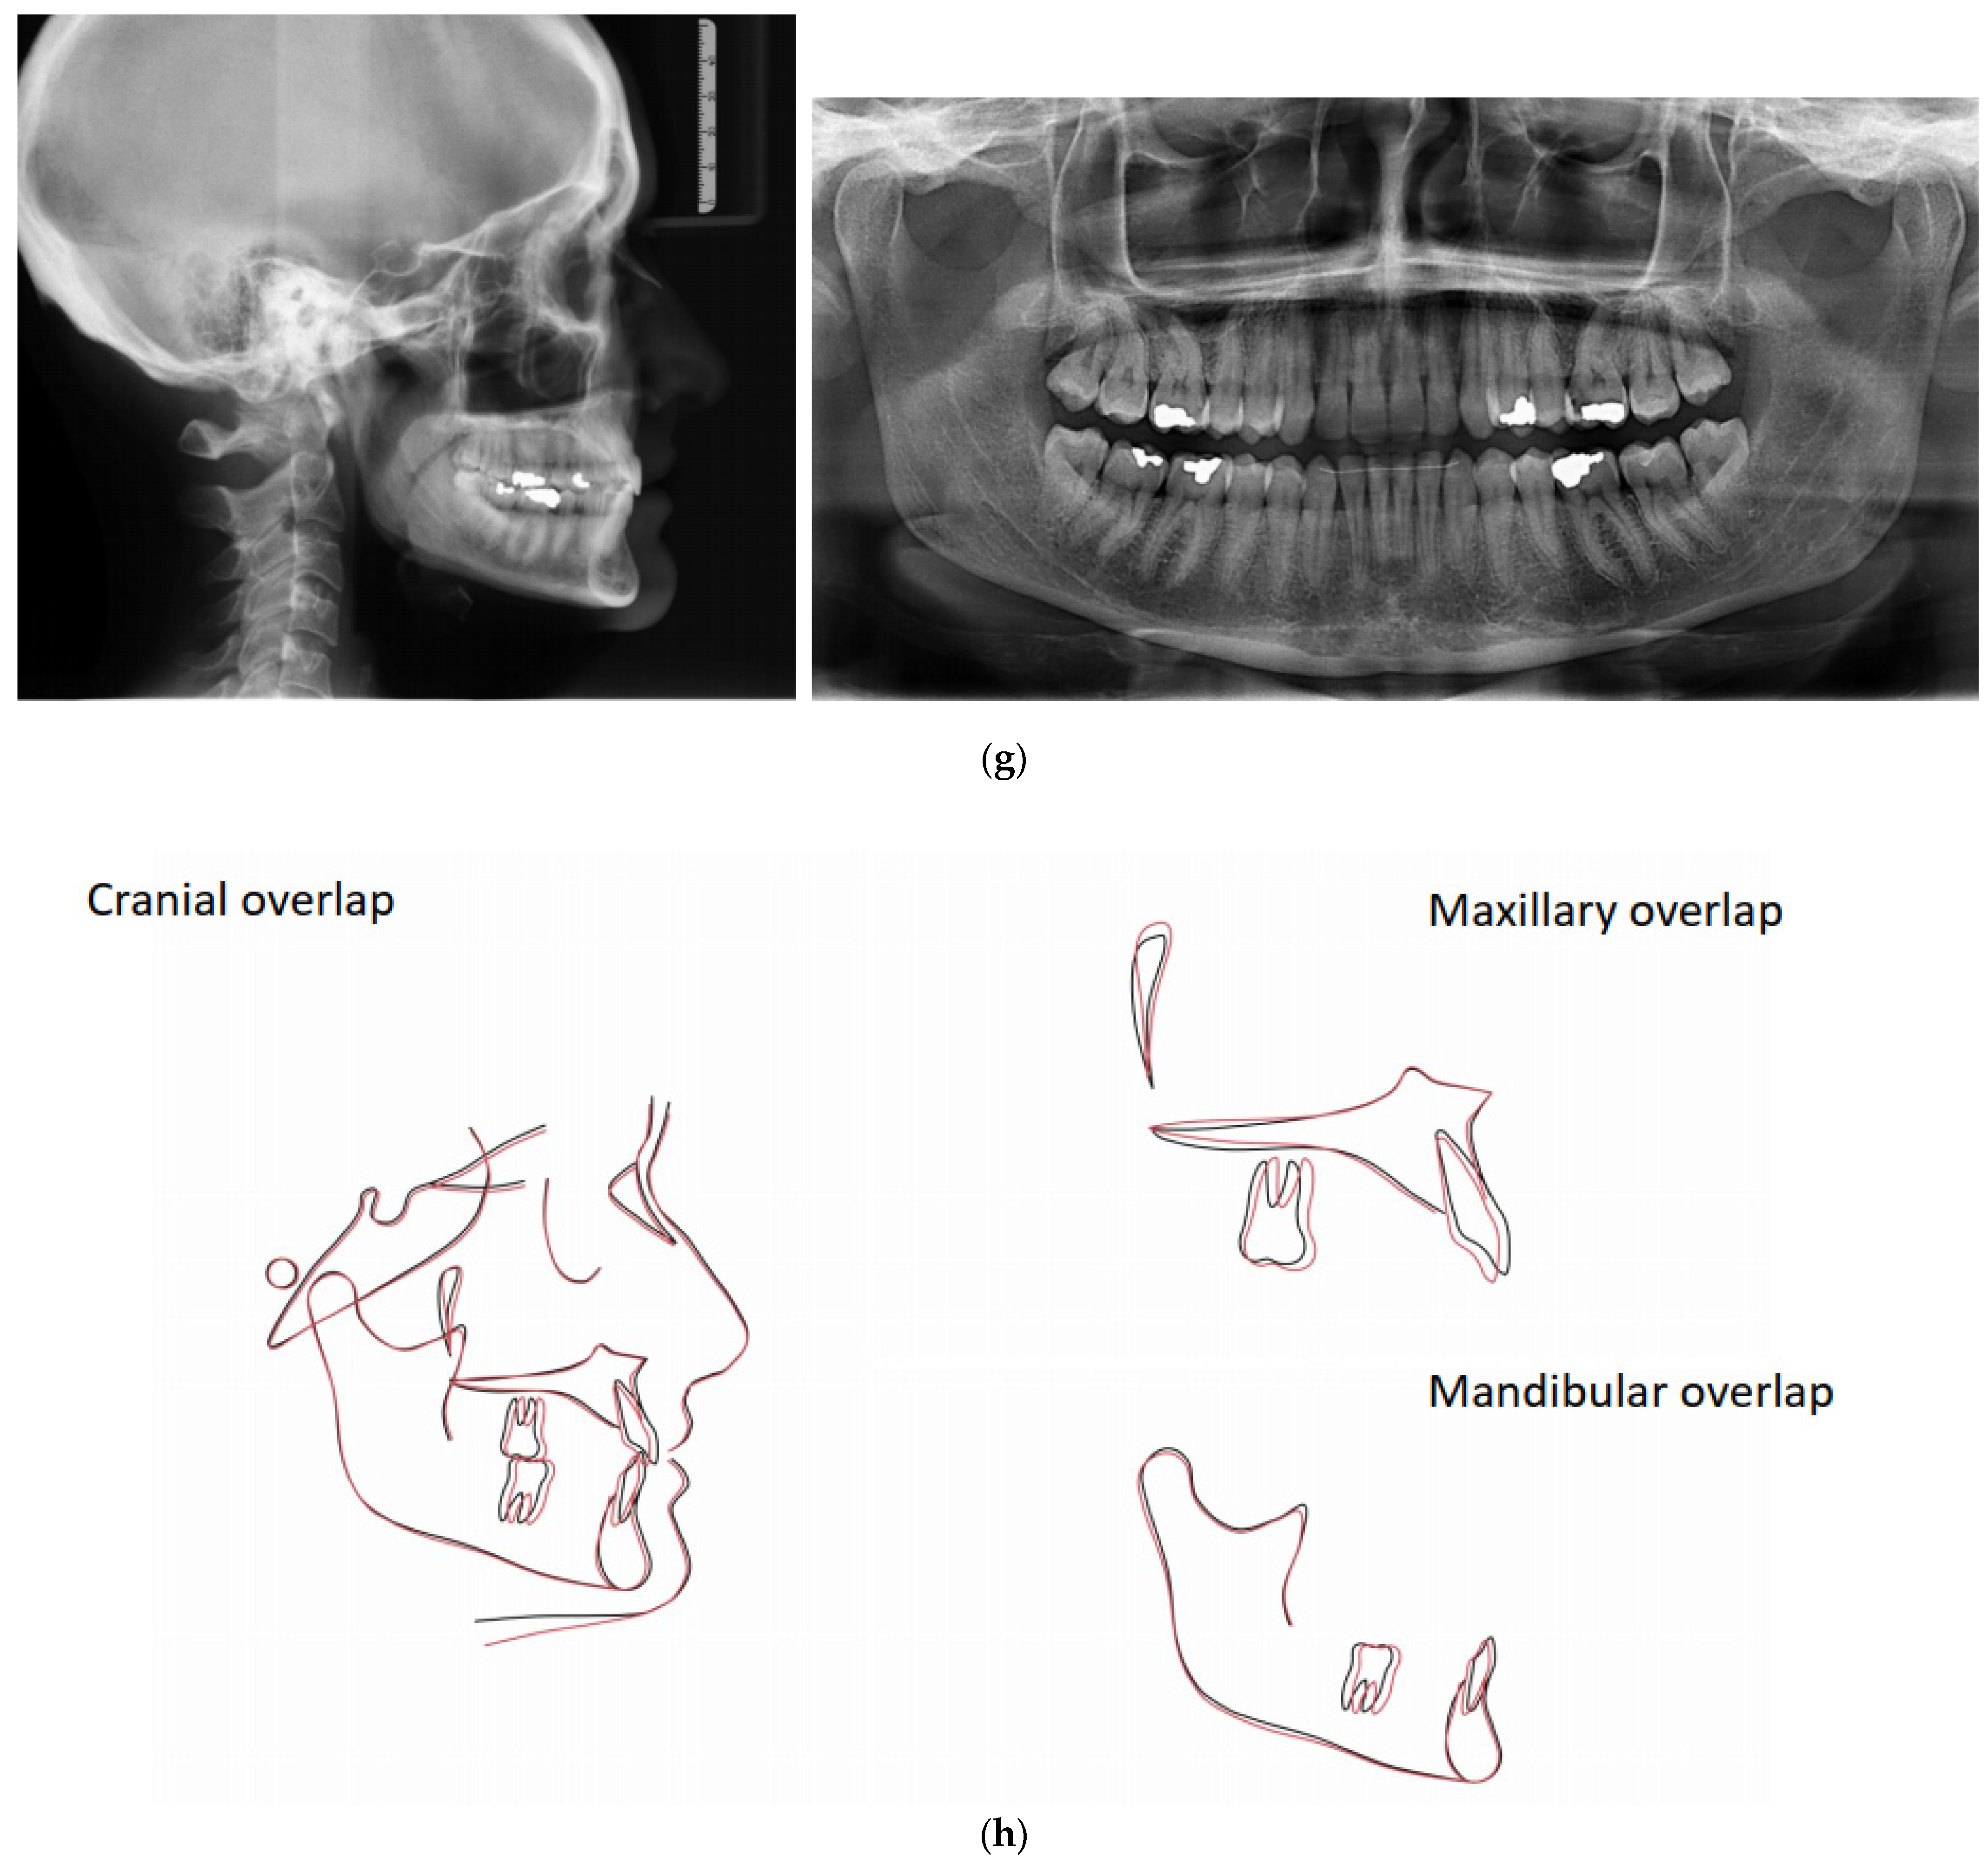

The patient was a 50-year-old male seeking orthodontic treatment for aesthetic reasons. His teeth were crowded, and he presented a concave profile with reduced lower facial height. An intraoral exam revealed a class II division 2 occlusal relationship and a severe deep bite in a hypodivergent facial type. There was severe crowding in both arches. The upper arch was narrow and presented a cross bite on 25. The upper midline deviated 2 mm to the right (Figure 5).

Figure 5.

(a,b) The initial images of the profile and frontal smile view and intraoral images and radiographs, including panoramic radiographs and a lateral cephalogram. (c) The digital setup performed for the treatment. (d,e) The treatment in progress with a Crozat appliance along with the aligners and lingual appliances. (f–h) Post-treatment images and a comparison with the initial images. (i) A superimposition of the pre- and post-treatment cephalograms.

Although the correction of transverse discrepancies with good torque control is challenging with both lingual and aligner techniques [24,34,38], Case 3 (Figure 5) had a similarly successful outcome. In that case, the treatment required significant transverse expansion, along with the elimination of the deep bite and resolution of the crowding in both arches. A Crozat appliance and a partial aligner with a bite ramp/plane was used for the initial four months. Temporarily opening the posterior bite enhanced the expansive effect of the Crozat and facilitated levelling of the lower curve of Spee via the direct use of lingual appliances on the mandibular arch. The intermolar width in the upper arch was increased from 53.6 mm to 57 mm and in the lower arch from 46 mm to 48.7 mm.

Once the expansion and deep bite correction had been accomplished, lingual appliances were bonded to align the upper arch, control the upper anterior inclination and torque (perfecting the crossbite), perform intrusion and control the lower incisor inclination.

The superimpositions show that the lower incisors proclined, as expected; therefore, the relative intrusion was shown. The full coverage of the occlusal surfaces typical of the full-time use of aligners has, in low-angle patients, limited lower molar extrusion. In cases 1 and 3, very minimal molar extrusion was noted since the intrusion of the lower incisors was relative one; due to the proclination of the lower incisors.